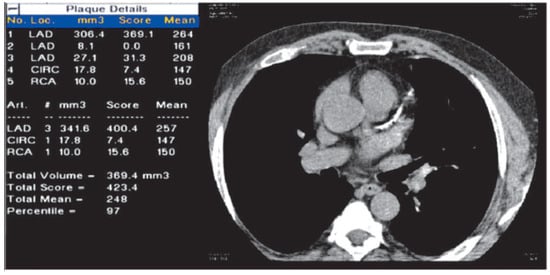

Coronary artery calcification (CAC) has been studied extensively since 1984. Reproducible measurements of CAC can be obtained only with electrocardiogram (ECG) triggering during image acquisition in computed tomography (CT). Visible CAC on a CT scan is 100% specific for coronary atherosclerosis (Figure 1) and is defined as a threshold of 130 Hounsfield units, which correlates with a calcium hydroxylapatite concentration of 102.7 g/cm3 [1]. CAC is significantly correlated with the amount of noncalcified plaque and is therefore a measure of the total plaque burden, including soft or “vulnerable” plaques, in unselected patients and in patients with unstable angina [2]. Calcium scoring has major limitations, for example, zero calcium does not exclude significant coronary artery disease.

Figure 1. Example of a 49-year-old asymptomatic subject with a Framingham risk score of 15% and a low HDL of 0.7 mmol/l, hypertension and obesity. The subject had extensive coronary artery calcification (Agatston score 423), in the left anterior descending artery, which puts the patient at higher risk for coronary events based on posterior probabilities using the Bayes formula: post-test risk increased from 15% to 45% with a 95% confidence interval of 31% to 60%.